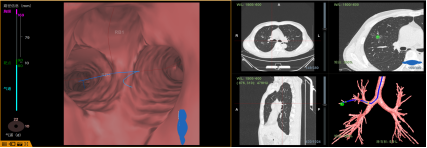

CBCT引导下多模态整合的一站式肺结节消融平台

基于锥形束CT(CBCT)引导、融合术前规划与术中实时干预的肺结节精准诊疗体系。该体系整合了导航技术、径向超声(R-EBUS)、共聚焦激光显微内镜(CLE) 以及冷冻/射频消融等多种前沿技术,实现了从路径规划到精准执行的一站式解决方案。

导航“GPS”定位跟踪

多种技术核实“身份”

精准式打击(冷冻/射频)